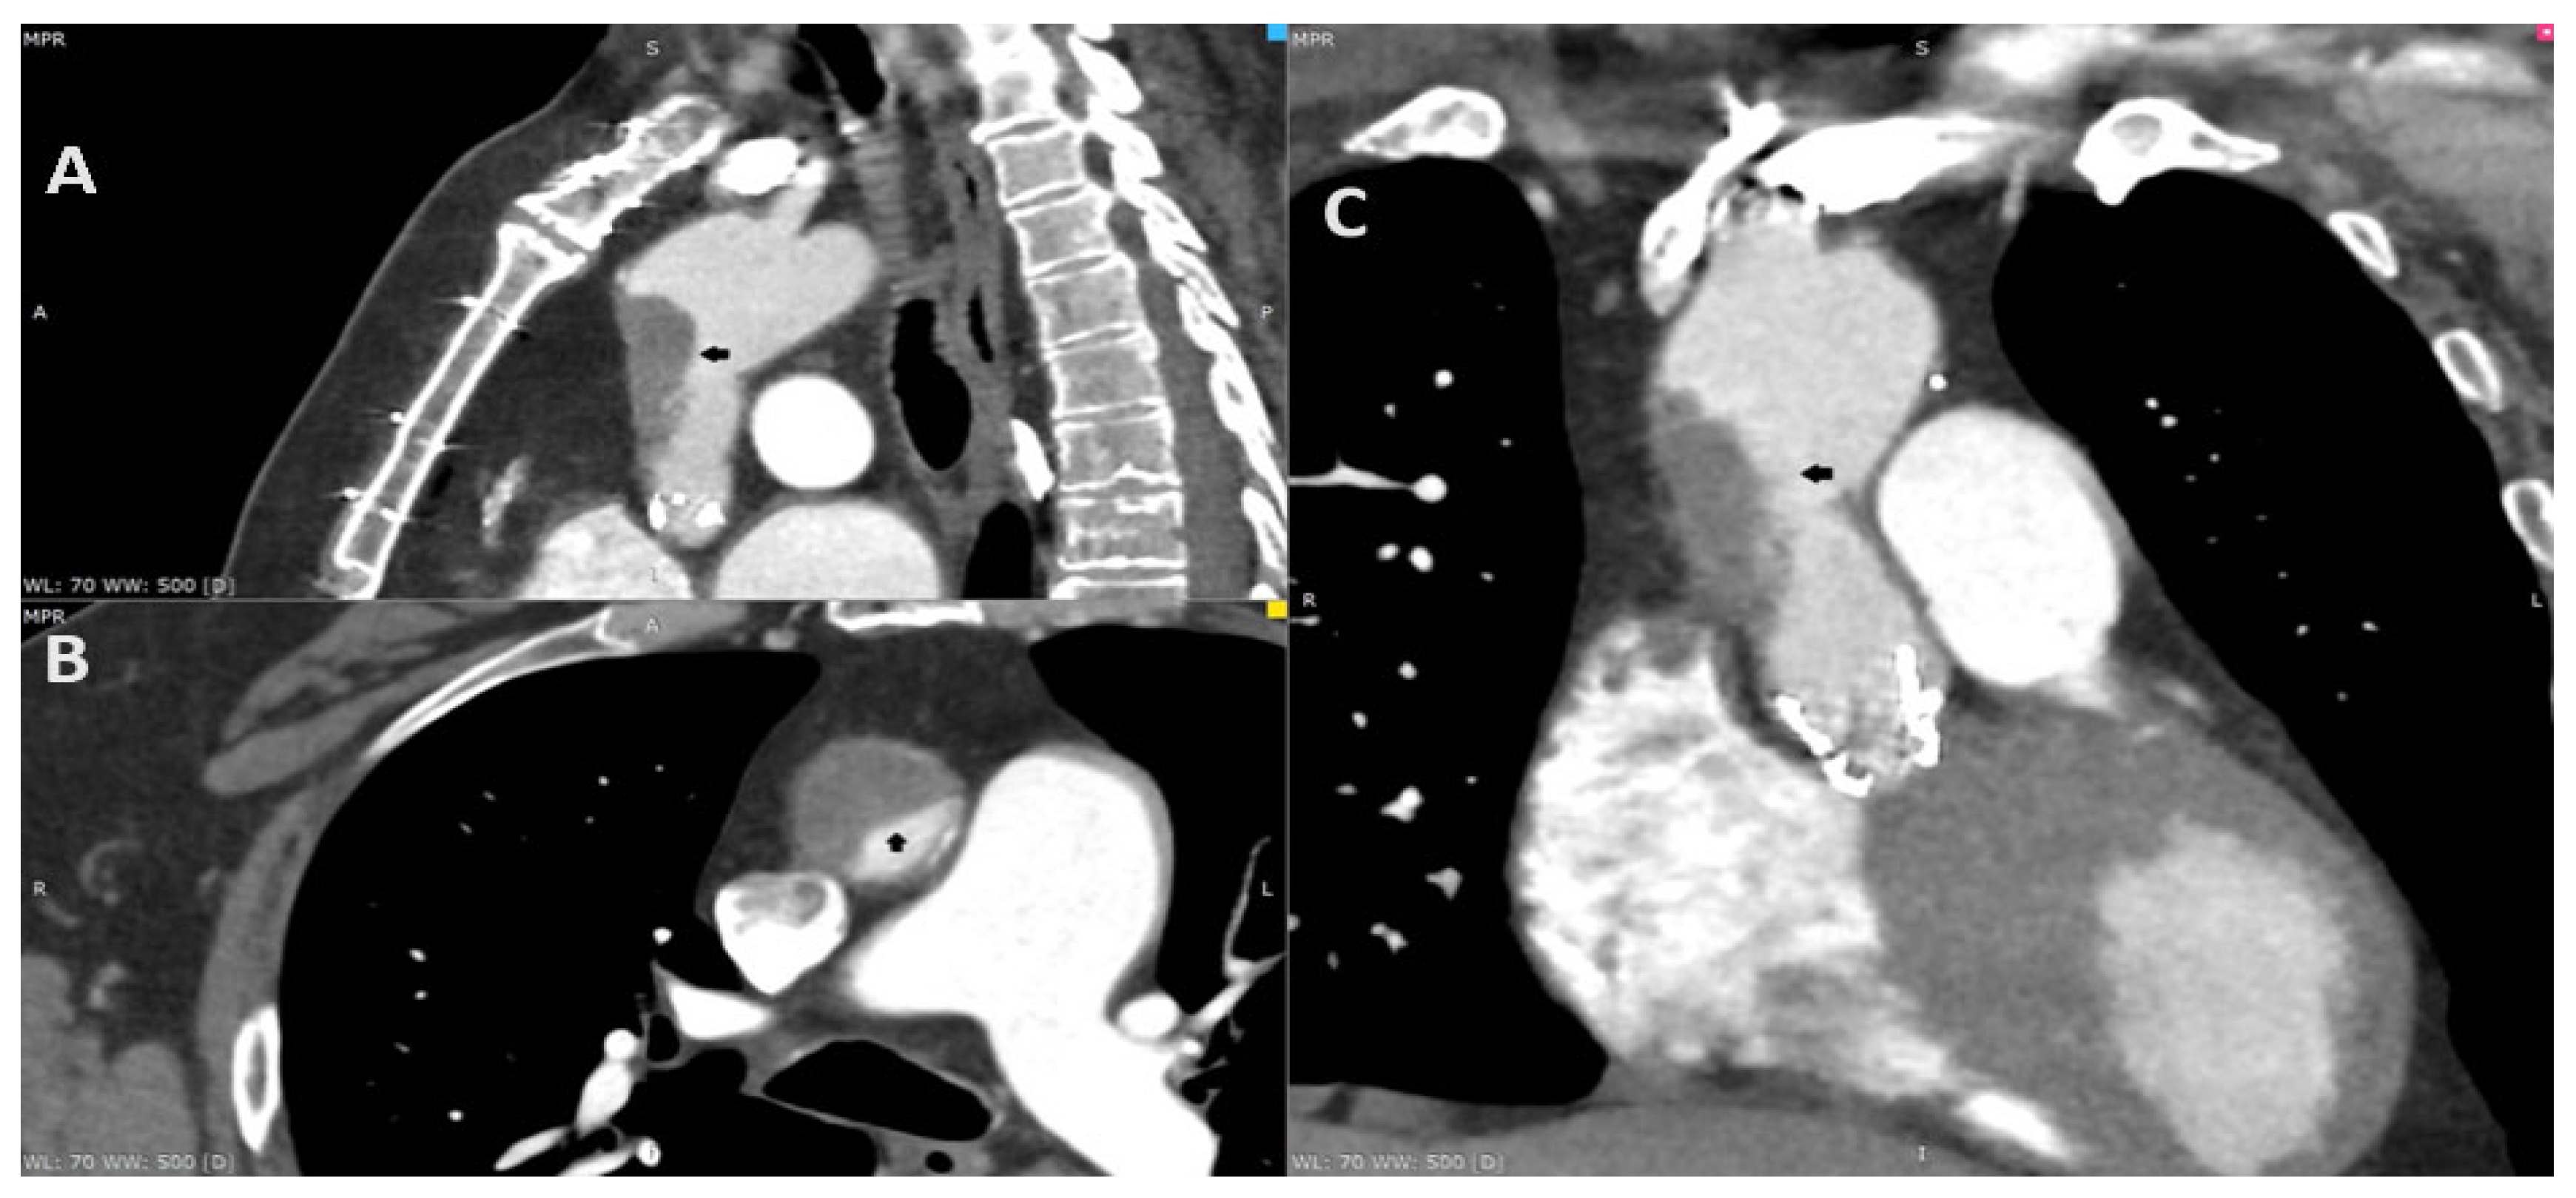

A 69-year-old male complaining of recurring chest pain, episodes of syncope and visual distortion was admitted to the hospital. His past medical history included the replacement of the ascending aorta with surgical aortic valve replacement (SAVR) in 2011 due to aortic aneurysm and aortic stenosis (Bentall procedure). He underwent transcatheter aortic valve implantation (TAVI) in 2021 due to the degeneration of aortic valve bioprosthesis, using a 26 mm balloon-expandable Sapien 3 Ultra (Edwards Lifesciences, Irvine, CA, USA). The treatment course after TAVI involved longitudinal single antiplatelet therapy (SAPT)—aspirin. In addition, he reported reduced exercise tolerance since the TAVI procedure. The coronarography in 2011 and angio-CT in 2021 excluded the significant coronary artery disease before operations. The angio-CT, including the aorta and head, at the current hospitalization found the thrombosis of the ascending aorta graft causing 80% stenosis (A–C; black arrow). Furthermore, due to the resolution of the neurological dysfunction, the patient was diagnosed with a transient ischemic attack (TIA). The transthoracic echocardiography revealed an increase in gradient through aortic valve bioprosthesis—a mean gradient of 24 mm Hg. The low-molecular-weight heparin (LMWH) in therapeutic dose was initiated. Despite the increase in cardiac enzymes, the chest pain and the diagnosis of non-ST elevation myocardial infarction (NSTEMI), the coronarography was not performed due to the risk involving the dislocation of the thrombi. After three days, the control CT displayed a significant reduction in the thrombus. The patient consulted with the Heart Team and was transferred to a higher reference clinical hospital with the availability of the cardiac surgery department.